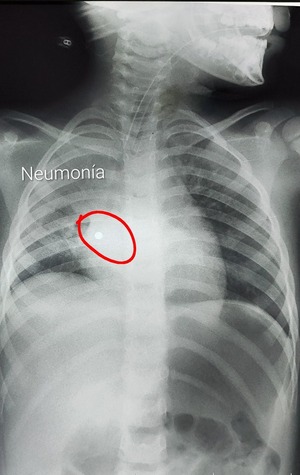

Paraguay se destaca entre los países con mayor cobertura de vacuna contra el VSR | Unicanal

111 39 9

Paraguay se destaca entre los países con mejores resultados en la protección de recién nacidos contra el virus respiratorio sincitial (VRS). Durante el Congreso de la Sociedad Latinoamericana de Infectología Pediátrica (SLIPE 2025), Paraguay se destacó... [Leer más]